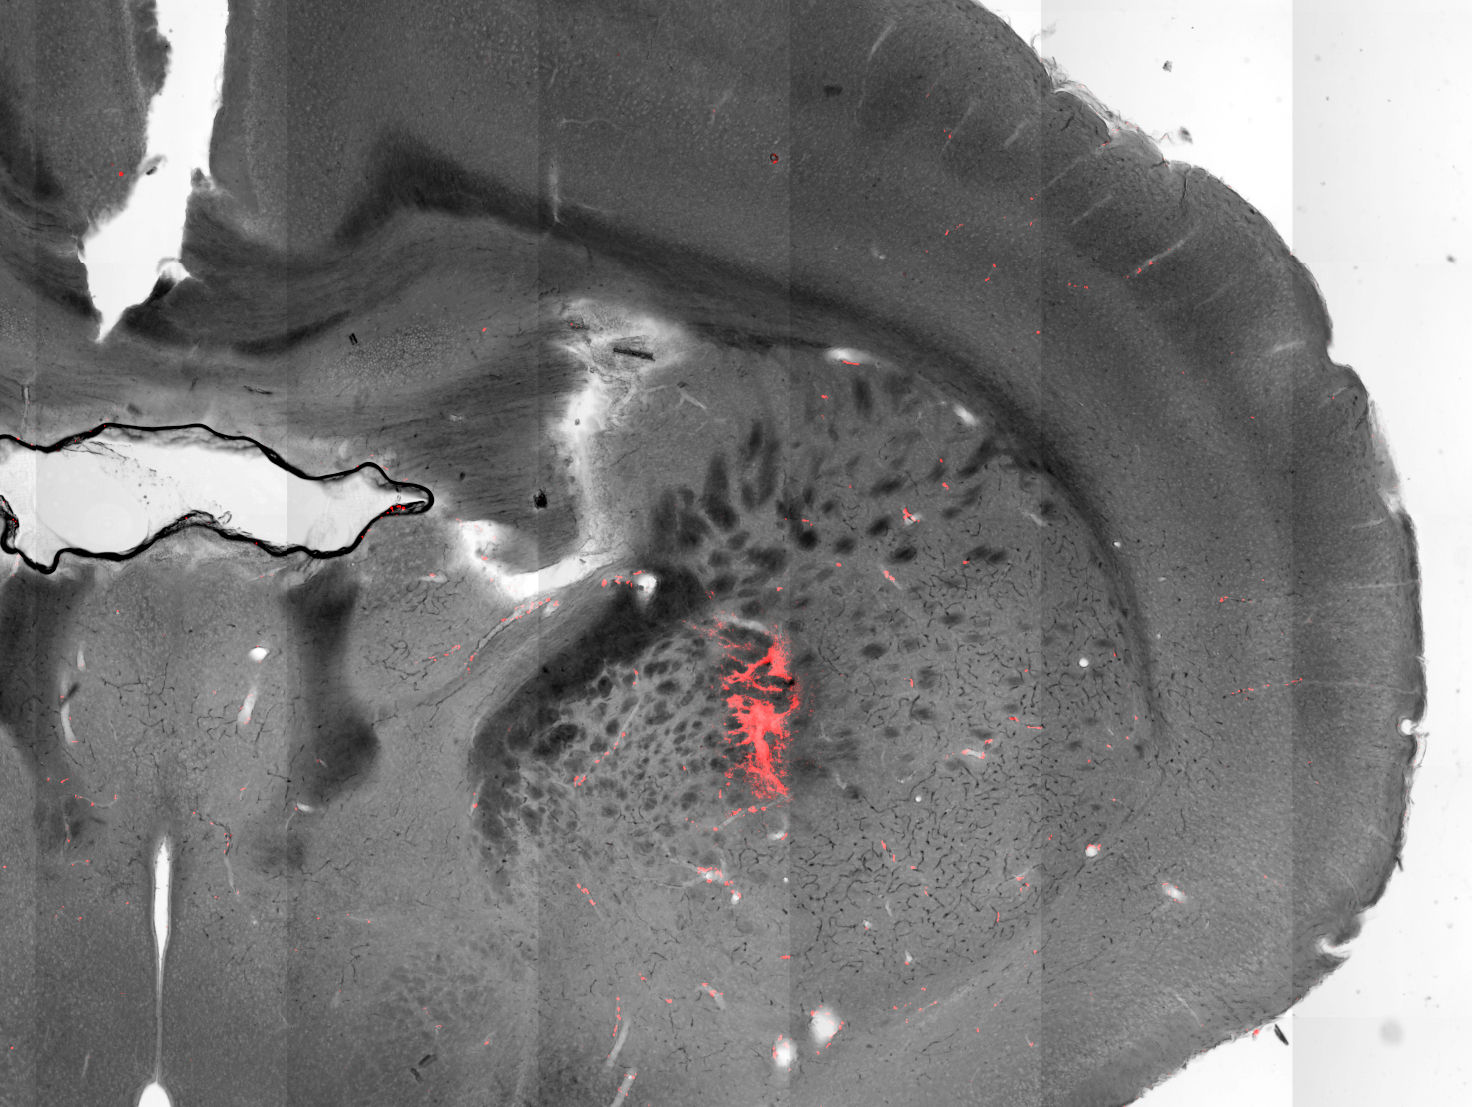

Scientists have used magnetic nanoparticles to stimulate neurons deep in the brain to evoke body movements of mice. This image shows a section of a mouse brain with injected magnetic nanoparticles (colored red) covering targeted cells in the striatum. Credit: Munshi et al, eLife